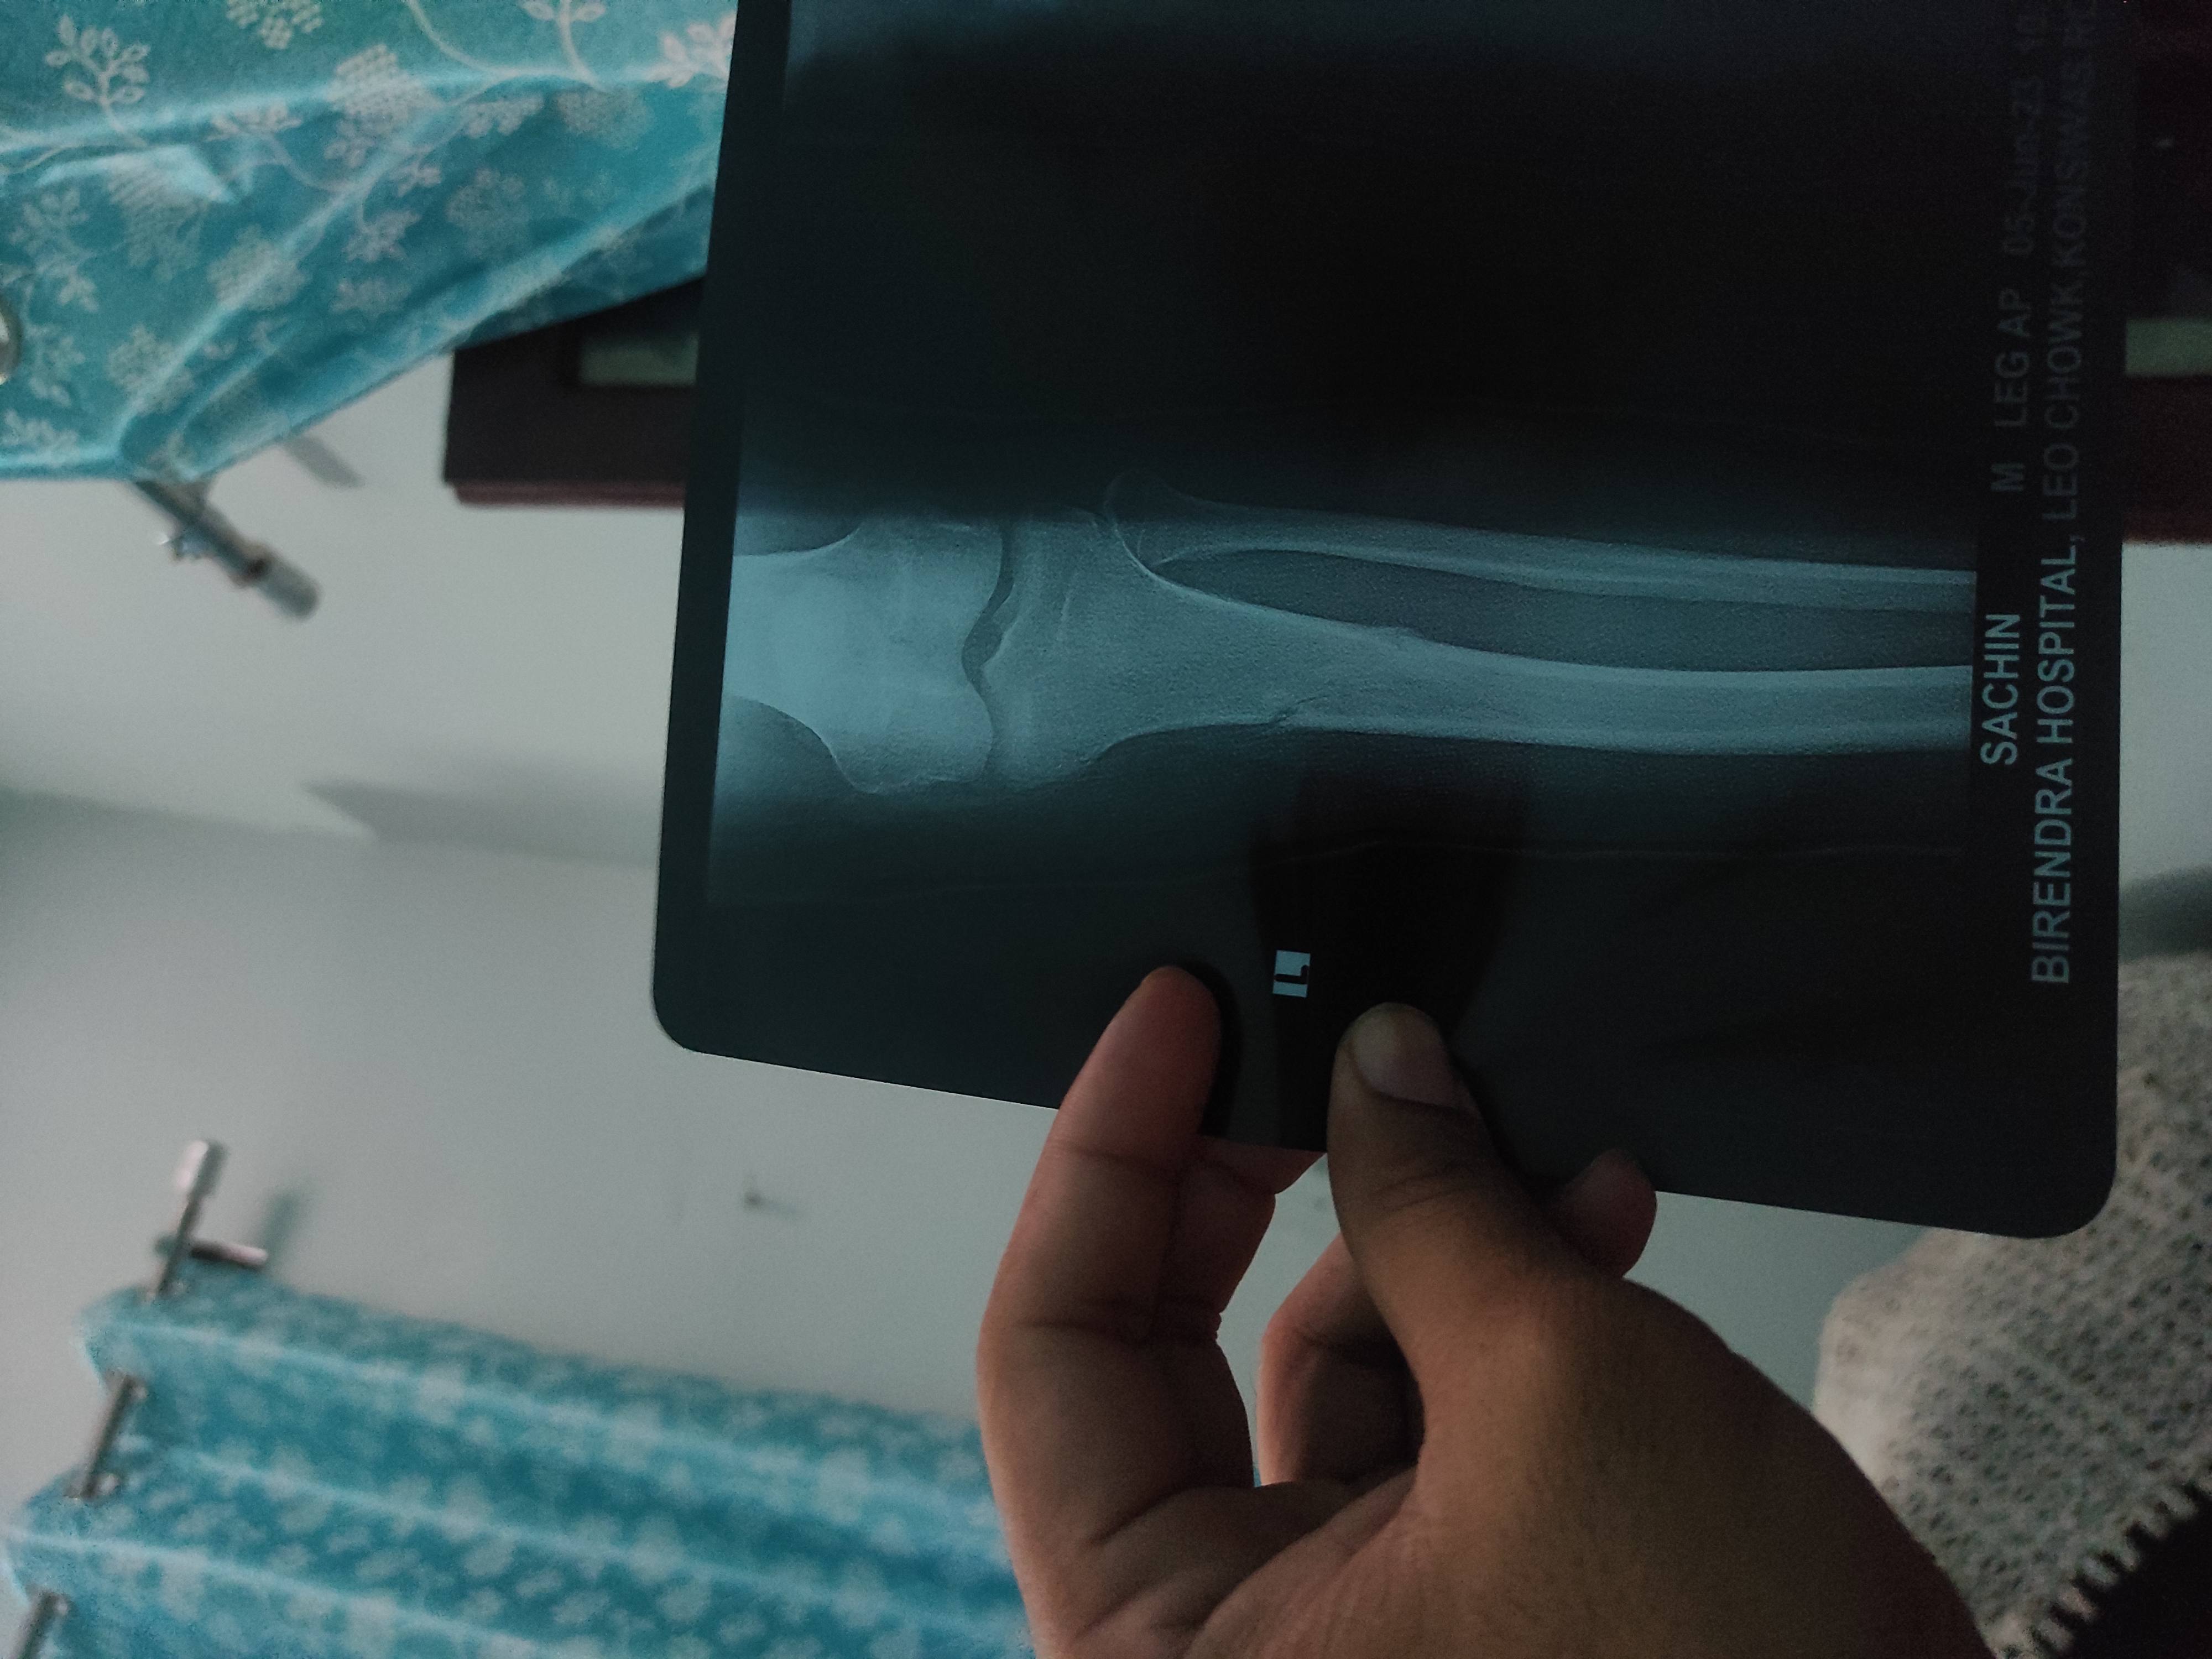

Sachin

Sir Muje tibiya me fracture hua tha 45 days plaster raha hai but doctor kah raha h 10 days or but i cut the plaster because i have no pain and ab knee ligament me pain hota hai band nai hota and X ray me dekh ke bata do sai hai ya nai that time